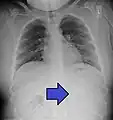

Multiple button batteries in the stomach